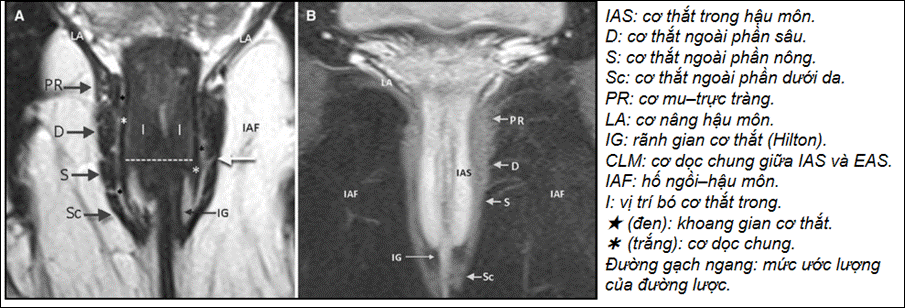

Chú ý:

●Mốc xác định vị trí 1/3dưới cơ thắt ngoài (gồm bó dưới da (Sc) và bó nông (S)): sử dụngDentate line(hoặc khoảng25–30% chiều dài ống hậu môn từ lỗ ngoài) làm mốc chia.

→ trên MRI ước lượng :Dentate line~ IAS mỏng lại một cách rõ rệt (dọc từ trên xuống dưới) hoặc khoảng cách từ rìa ngoài hậu môn (anal verge) tới dentate line ~2–2.5 cm(một số nghiên cứu

|

→ dưới đường lược ( 1/3 dưới cơ thắt ngoài) → rò độ thấp → Trên đường lược ( trên 1/3 dưới cơ thắt ngoài) → rò độ cao |